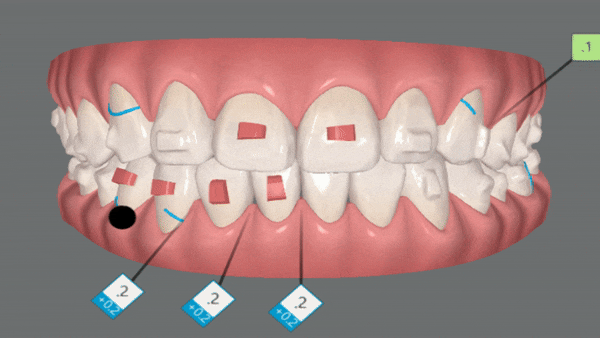

인비절라인은

환자와 상담부터 치료과정, 후까지

모든 과정을 디지털로 가능할 수 있도록 하고

다양한 유형의 치료케이스를 편안하고 정교하게 치료할 수 있도록

지속적으로 발전하는 글로벌 투명교정장치 입니다.

유펜바른치과 김승우 원장님은 정밀진단, 검토, 수정, 승인 등

인비절라인이 보유한 빅테이터를 바탕으로

치료계획을 클린체크를 통해 시각적으로 구현합니다.